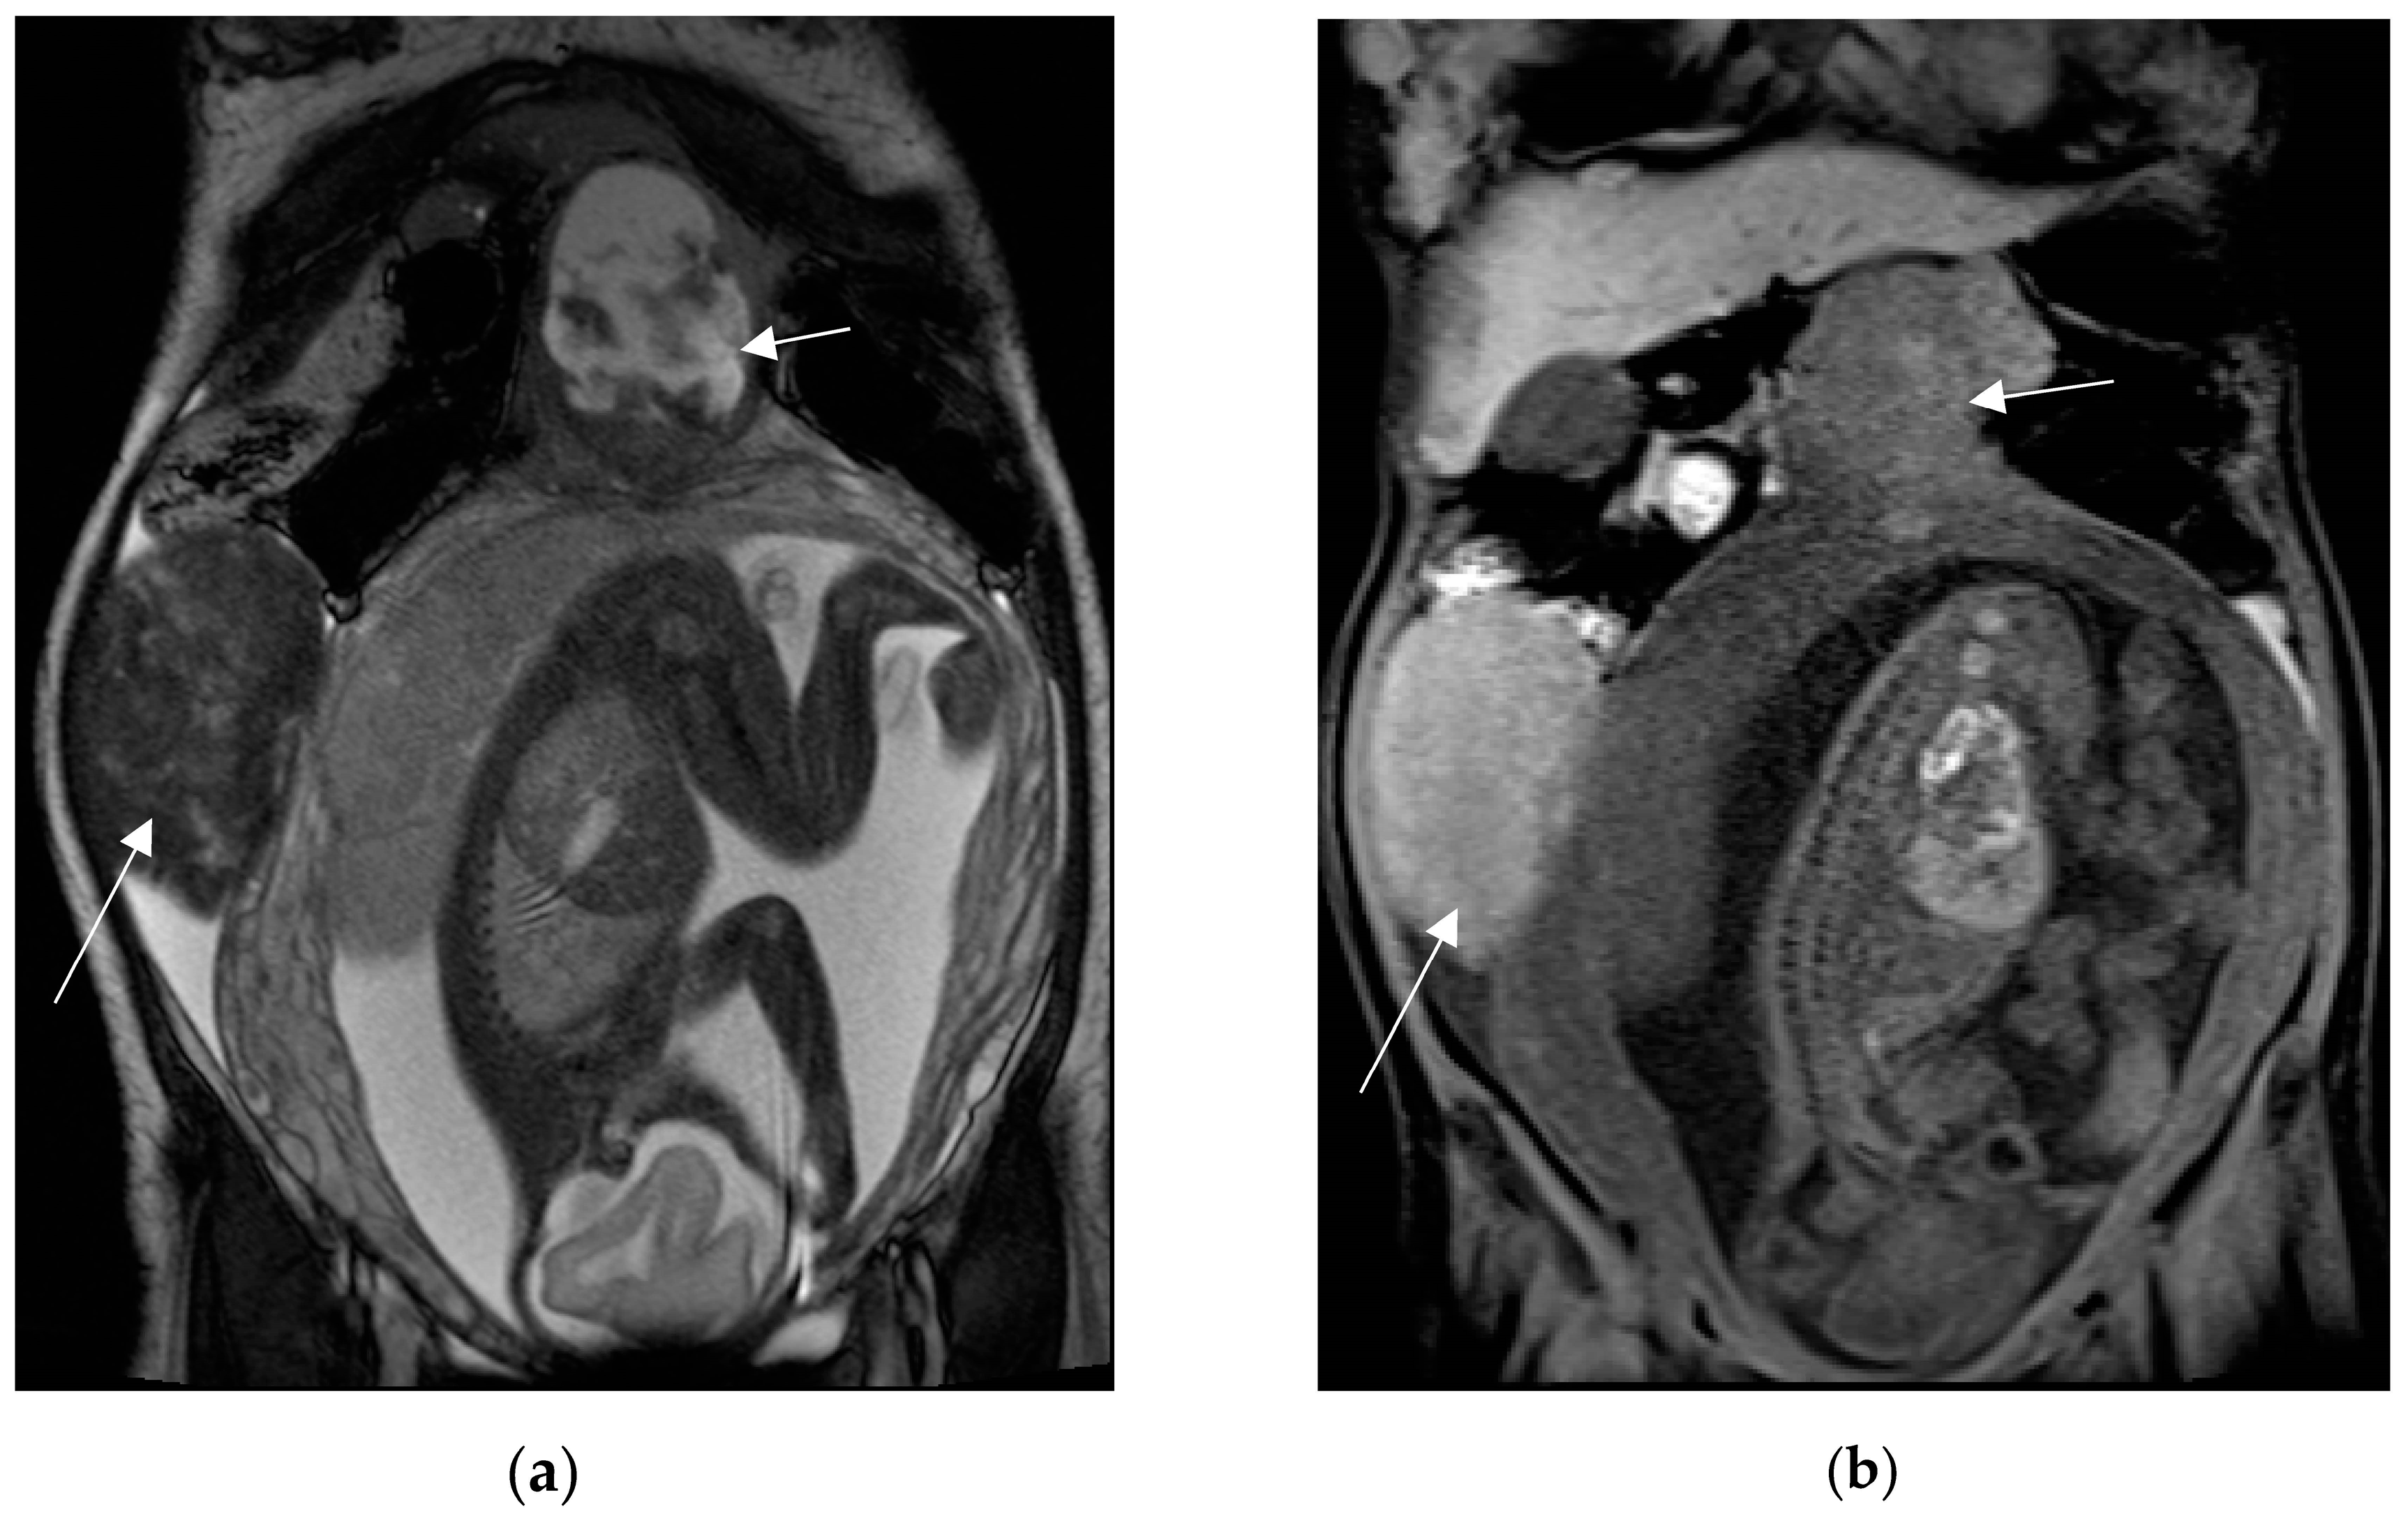

MRI demonstrates pancreatic enlargement and oedema, with reduced intensity on T1-weighted images and increased intensity on T2-weighted images (Figure 6).

Figure 6.

A 27-year-old pregnant woman with acute abdominal pain and elevated lipase levels (451 UI/mL). Coronal (a) and axial (b) T2-weighted sequences show peripancreatic fat stranding and fluid (arrows), interdigitating through pancreatic parenchyma. These findings are consistent with acute pancreatitis.

On DWI, acute early pancreatitis shows restricted diffusion and lower ADC values than the spared parenchyma [65]. In severe pancreatitis, necrotic foci within the parenchyma are hypointense on T1-weighted images and hyperintense on T2-weighted images, compared to the non-necrotic gland. Parenchymal haemorrhage can be detected at spotted or patchy high-signal intensity (like “salt”) on T1-weighted fat saturated sequences. Peripancreatic abnormalities, such as fluid collection, edema or fat stranding are better identified on fluid-sensitive sequences, appearing as high-intensity signals surrounding the gland. MRCP sequences acquired with respiratory gated-thin sections, are best suited to depict biliary and pancreatic ductal dilatation, allowing the detection of gallstones, shown as filling defects in the gallbladder and biliary tract [3,41,66]. The majority of pregnant patients with AP do not have complications. Gilbert et al. reported a complication rate of 1.44%, all of which were acute peripancreatic fluid collections (APFC) [67]. APFC occur in 50% of interstitial edematous pancreatitis. They are usually rounded with thin walls, often located in the lesser sac or anterior pararenal space. MRI is better than CT for detecting solid content or internal hemorrhage in APFC [68]. Vascular complications include arterial pseudoaneurism and venous thrombosis, most commonly involving splenic vessels; these abnormalities are typically assessed on contrast-enhanced MR angiography in non-pregnant populations, but can also be assessed with flow sensitive time-of-flight angiographic techniques [66].